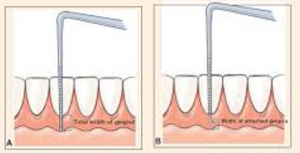

„Prikreplonka” - mi ez és miért nem elég?

Általában ZKPD a fogak körül szélessége tartományok 4-9 mm. Mérjük meg a szélessége ZKPD nem nehéz. Először is, a szélessége mentén mérik elszarusodó fogíny vagy a „fehér csíkos” a mukogingivalnoy határt. Ezután sulkusa mért mélység és kivonjuk a teljes szélességben. Így megkapjuk a szélessége elszarusodott feszes íny.

Ha a helyzet a képen a bal növelése nélkül ZKPD is lehetne elhagyható, bár az eredmény egészen elfogadható, akkor a jobb oldali a képen - kábel eltávolítása és növeli ZKPD szükséges minden esetben - van egy fog vagy az implantátum. Podiatrist köteles azt kell figyelni, mert attól függ a siker ortopédiai kezelést.